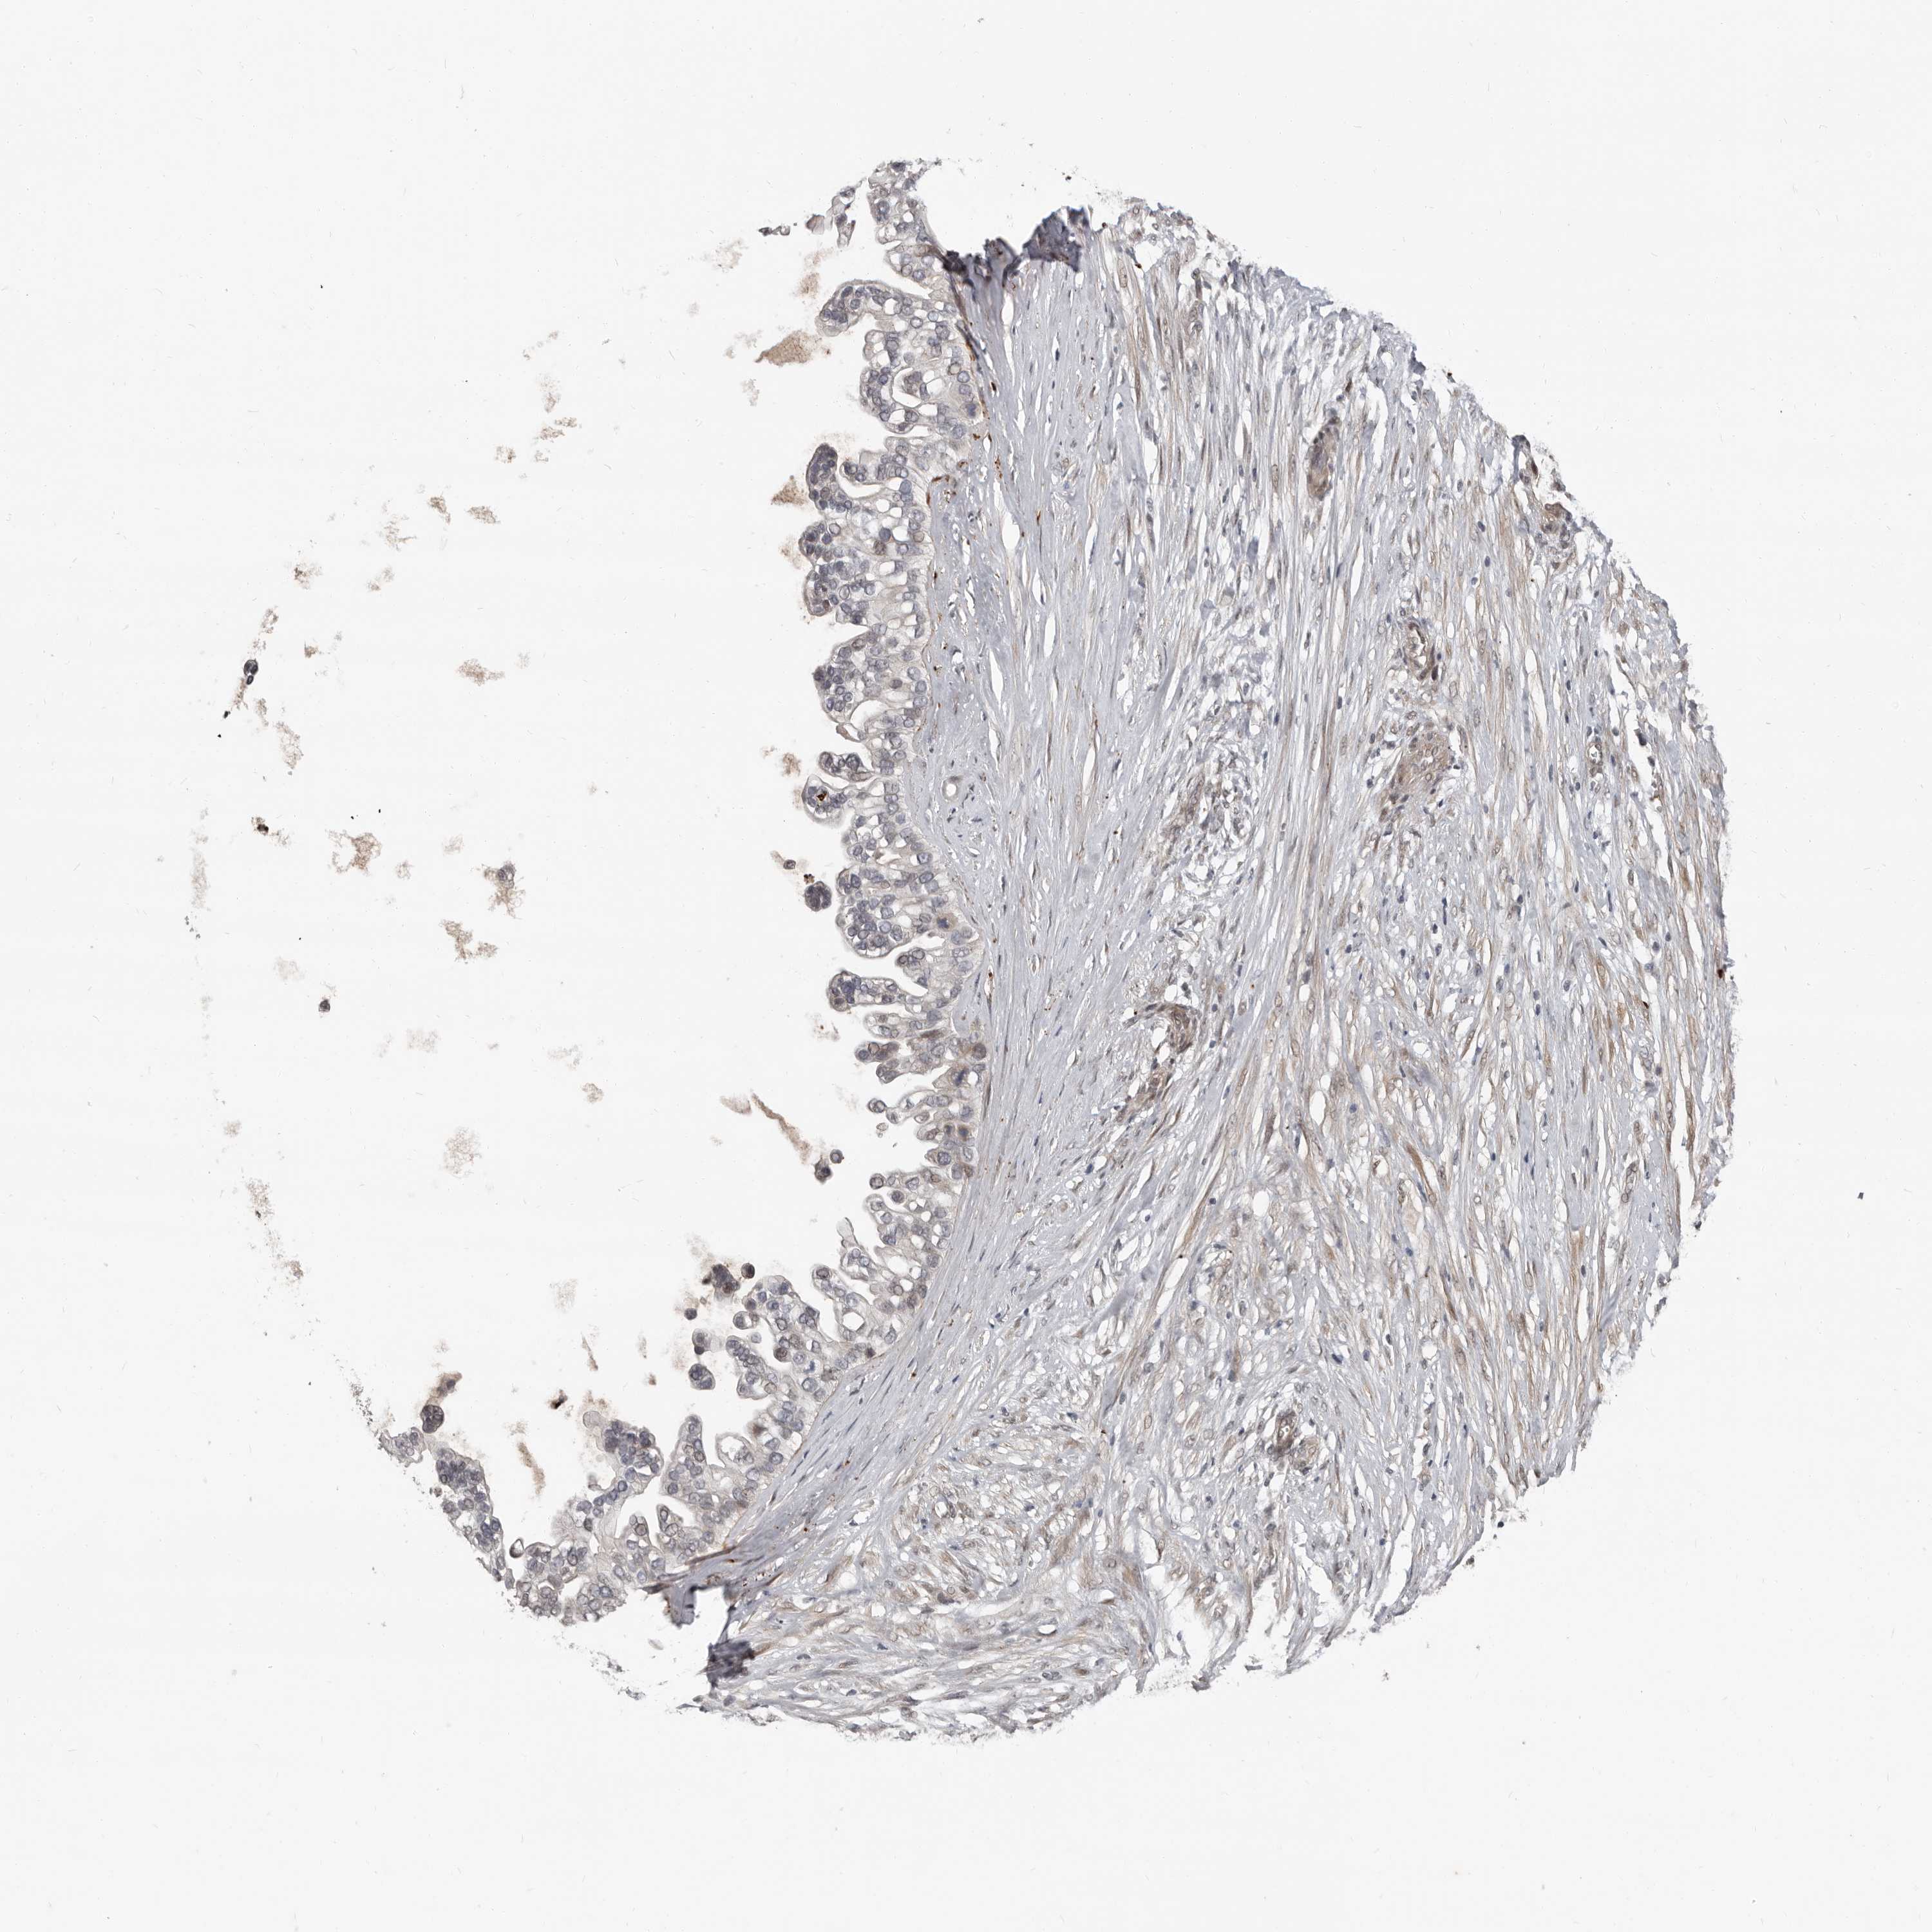

OVARIAN CANCER - Protein expressioni

A mouse-over function shows sample information and annotation data. Click on an image to view it in a full screen mode. Samples can be filtered based on level of antibody staining by selecting one or several of the following categories: high, medium, low and not detected. The assay and annotation is described here.

Note that samples used for immunohistochemistry by the Human Protein Atlas do not correspond to samples in the TCGA dataset.

Antibody stainingi

Antibody staining in the annotated cell types in the current human tissue is reported as not detected, low, medium, or high, based on conventional immunohistochemistry profiling in selected tissues. This score is based on the combination of the staining intensity and fraction of stained cells.

Each image is clickable and will lead to virtual microscopy that enables deeper exploration of all samples and also displays staining intensity scores, fraction scores and subcellular localization as well as patient and tissue information for each sample.

Antibody HPA029165

Antibody HPA029167

Antibody CAB028574

Cystadenocarcinoma, serous, NOS

Carcinoma, endometroid

Cystadenocarcinoma, mucinous, NOS

Carcinoma, NOS